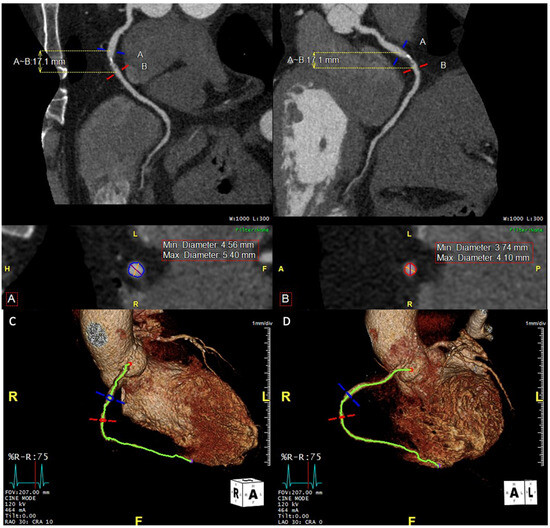

7.5. Chronic Total Occlusion (CTO)